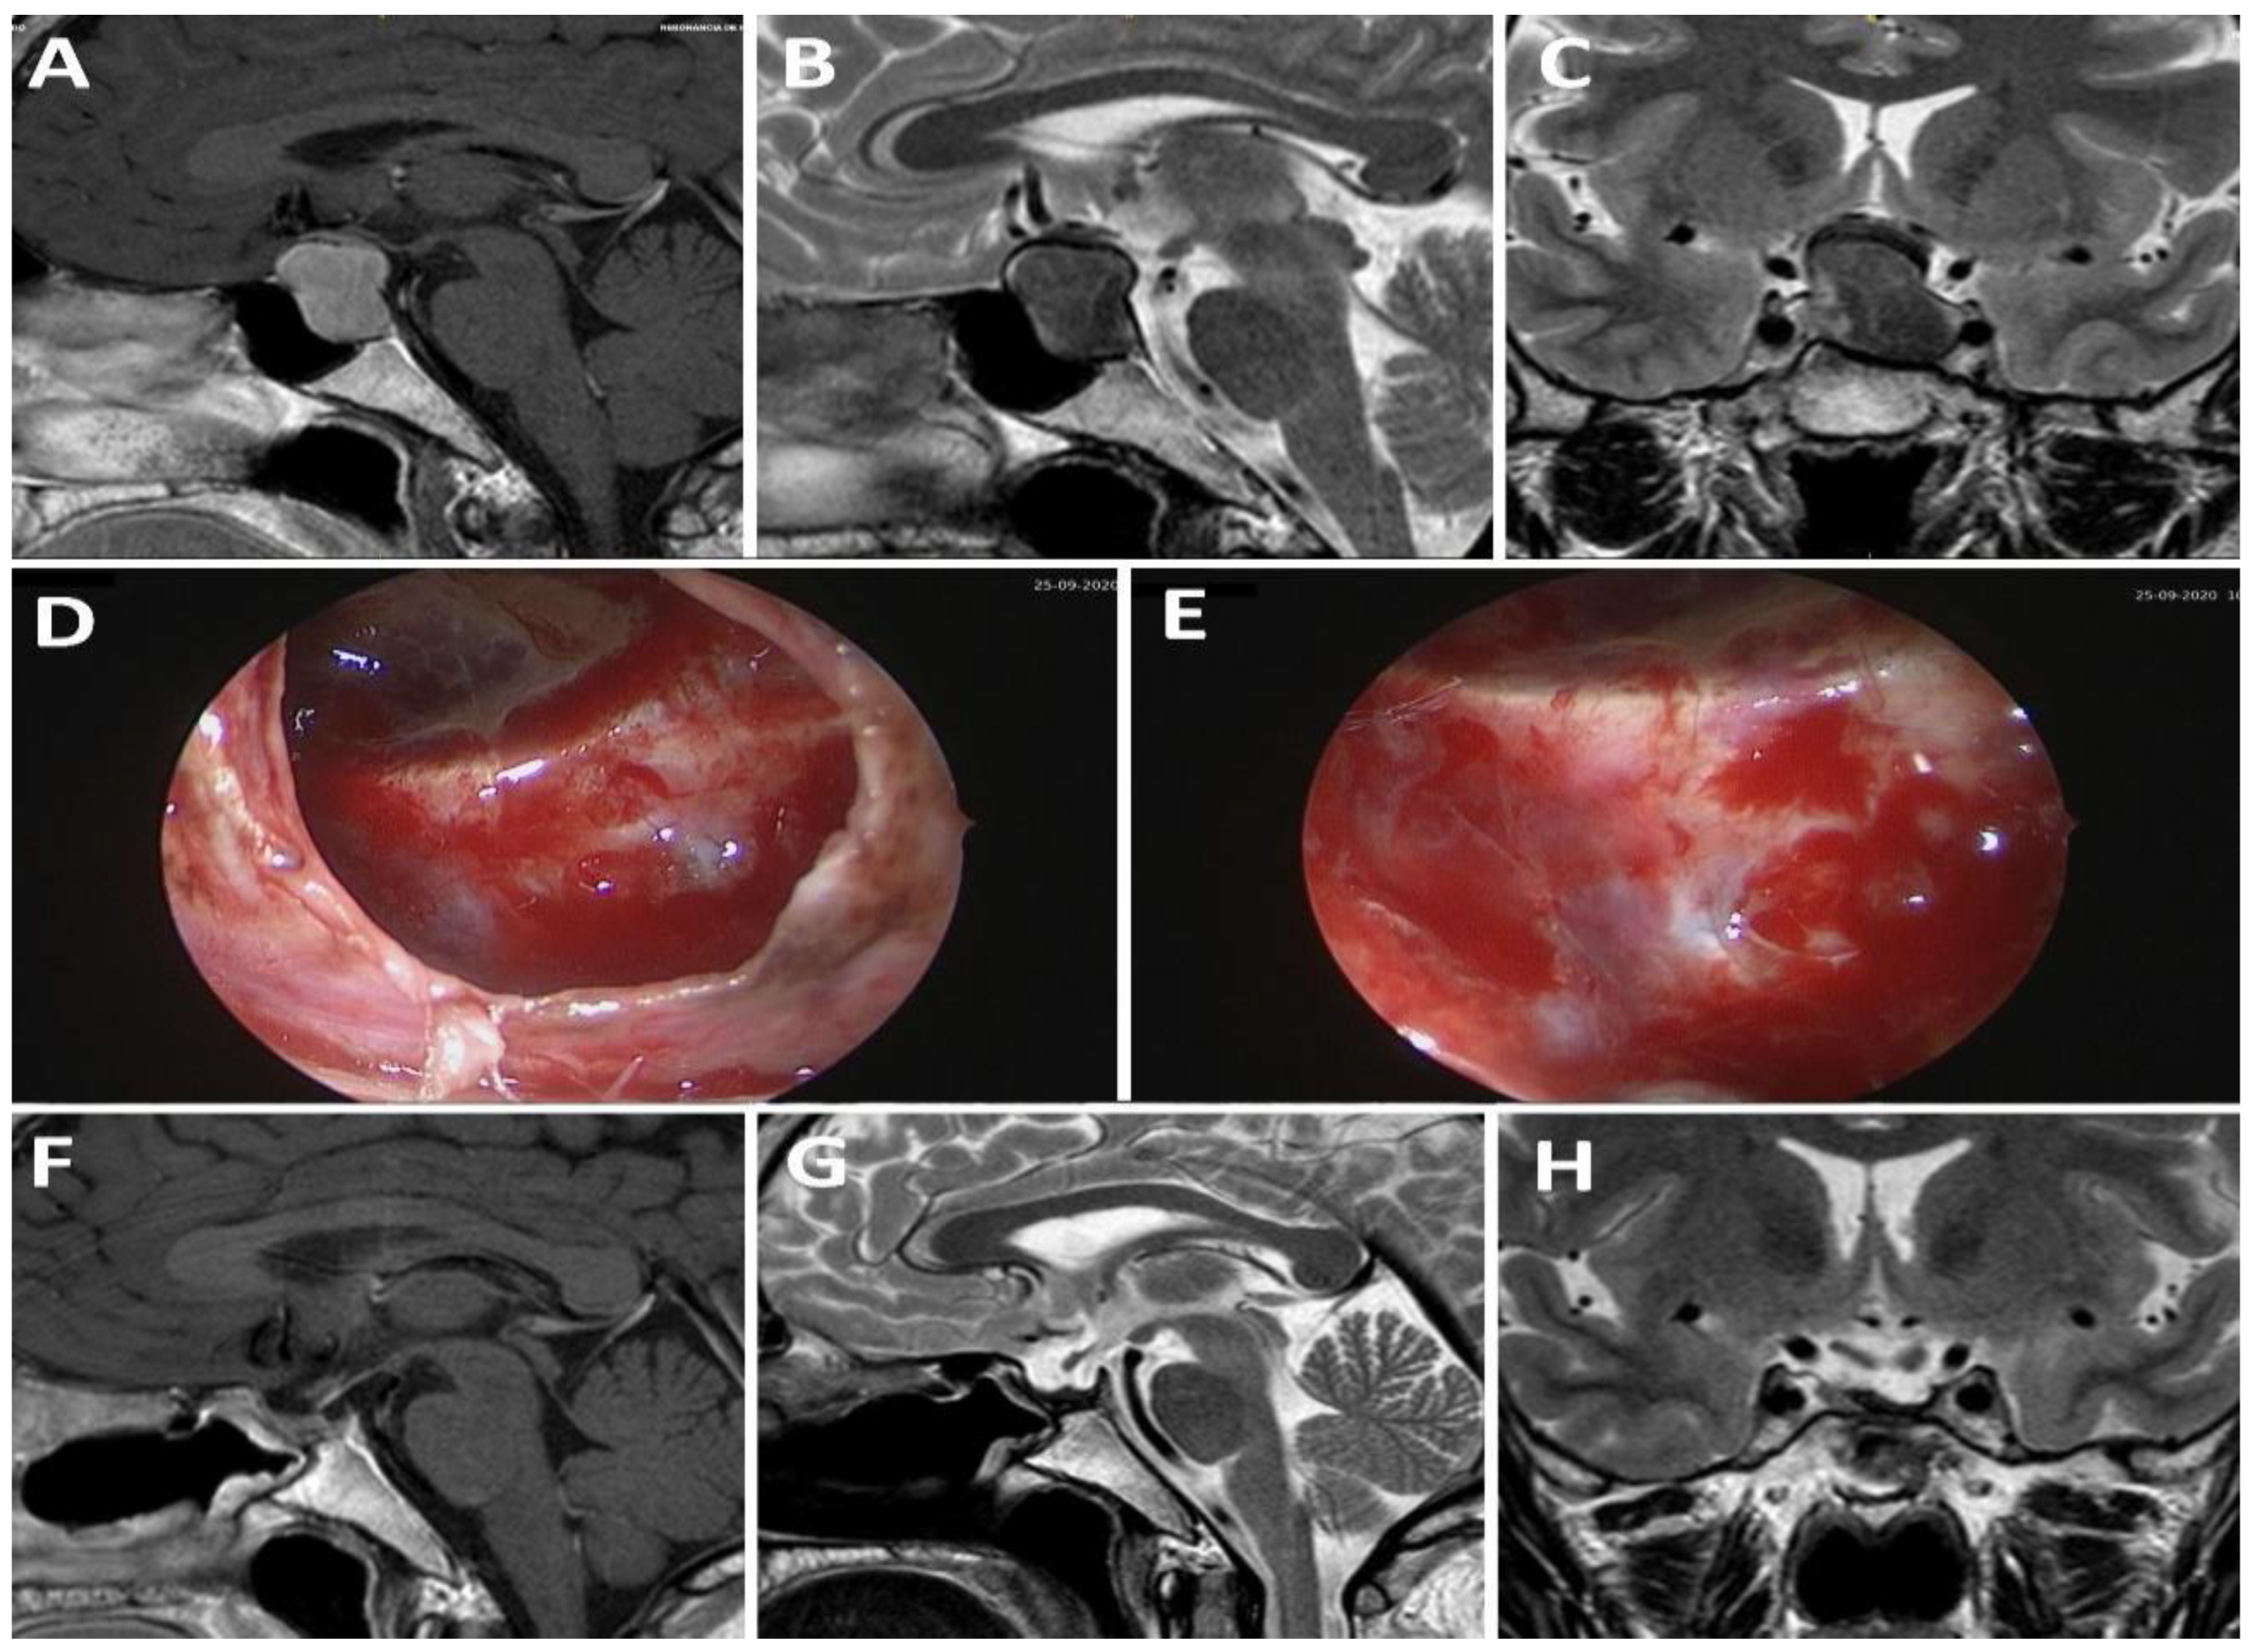

4.2.5. Differentiation Sellar Barrier Subtypes on MRI and during Surgery

- -

- Strong: barrier thickness more than 1 mm.

- Weak: barrier thickness less than 1 mm.

- Mixed: T1-weighted volumetric sequences displaying both types of thicknesses in different areas of the sellar barrier.

- Strong: gland and/or dura mater are observed on the roof of the pituitary fossa.

- Weak: roof composed only of arachnoid.

- Mixed: a portion of the roof is covered by gland or dura mater and another portion by arachnoid.

4.2.6. Correlation between MRI, Intraoperative Findings, and Risk of CSF Leakage